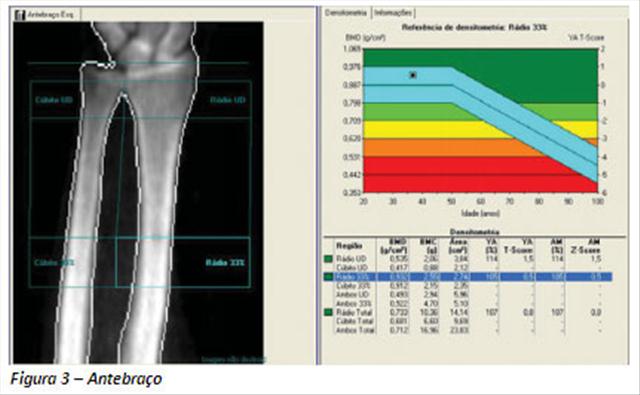

O método realiza medidas quantitativas da massa óssea em certos locais do corpo humano. No geral, as partes de interesse na obtenção das imagens para diagnóstico são o fêmur e a coluna vertebral, tendo em vista que as partes do corpo mais afetadas na osteoporose são: o colo do fêmur, a coluna, a pelve e o punho.